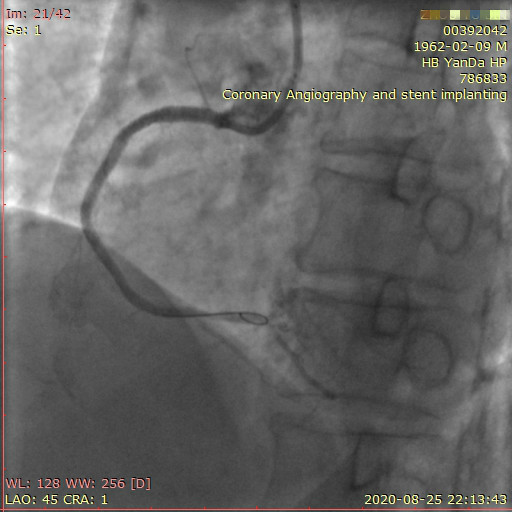

李先生右冠術前影像

術前,翟光耀主任還親自為李先生復查冠狀動脈造影,造影結果顯示:患者的前降支、回旋支、右冠等冠脈三支嚴重病變、嚴重鈣化,且均為彌漫性長病變,最重處99%以上管腔極嚴重狹窄。翟主任仔細閱讀造影結果后指出:結合李先生的實際情況,雖然微創介入手術難度比較大,但仍可行;李先生心臟三支主干動脈均存在極其嚴重的狹窄,每一支動脈均至少植入2-3枚支架,根據患者的耐受情況,李先生可能需要分3次分別對三支動脈進行介入手術;考慮到李先生路途遙遠,病情嚴重,不宜反復奔波,并且患者迫切要求能夠徹 底解決病痛,在病情允許的情況下,如果手術順利,爭取為患者進行“一站式”手術,一 次 性解決全部三支動脈病變!

李先生足位術前影像

李先生足位術后影像

手術方案確定之后,在心血管內三科趙景新主任、介入醫學科富孝晨主任的配合下,翟光耀主任親自擔任主刀,分別依次對李先生的三支動脈進行了完全血運重建。由于手術進展順利,李先生術中沒有任何癥狀,耐受良好,于是成功的將三支動脈“一站式”治療!術中,由于李先生左主干遠端分叉處存在嚴重病變,翟光耀主任選擇國際指南推薦的DK-mini-Crush技術,確保了分叉處兩支主干開口均萬無一失。據悉,DK-mini-Crush技術是目前冠脈分叉病變領域最為復雜及難以掌握的介入技術之一,對手術醫生經驗、體力均提出了極大的挑戰。極為擅長復雜介入技術的翟光耀主任卻用嫻熟的技術確保了李先生手術的成功。

冠狀動脈嚴重鈣化合并狹窄病變是冠脈介入的一大難題,血運重建難度大,成功率低,并發癥發生率高,該例患者的成功救治標志著我院冠脈介入水平又躍上了一個新的臺階。